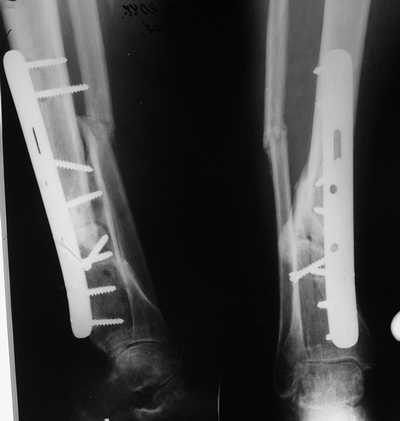

Male 54 years old, diabetic, blind in both eyes, with infected (MRSA) non union distal tibia after fracture 8 month ago. In acute phase treated by ORIF with LCP tibia and fibula. Treatment complicated by infection and after 6 month hardware was removed and treatment continued by cast fixation. You can see malposition of fragments In this stage beginning treated by Ilizarov fixation with use Hexapod system, allows anatomical position of fragments and you see signs of union.

Sorry, I wiil tray now pictures of my case.